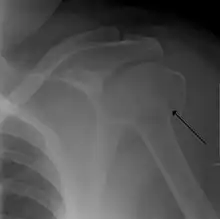

A displaced supracondylar fracture in a child

Fracture dislocation of the right shoulder